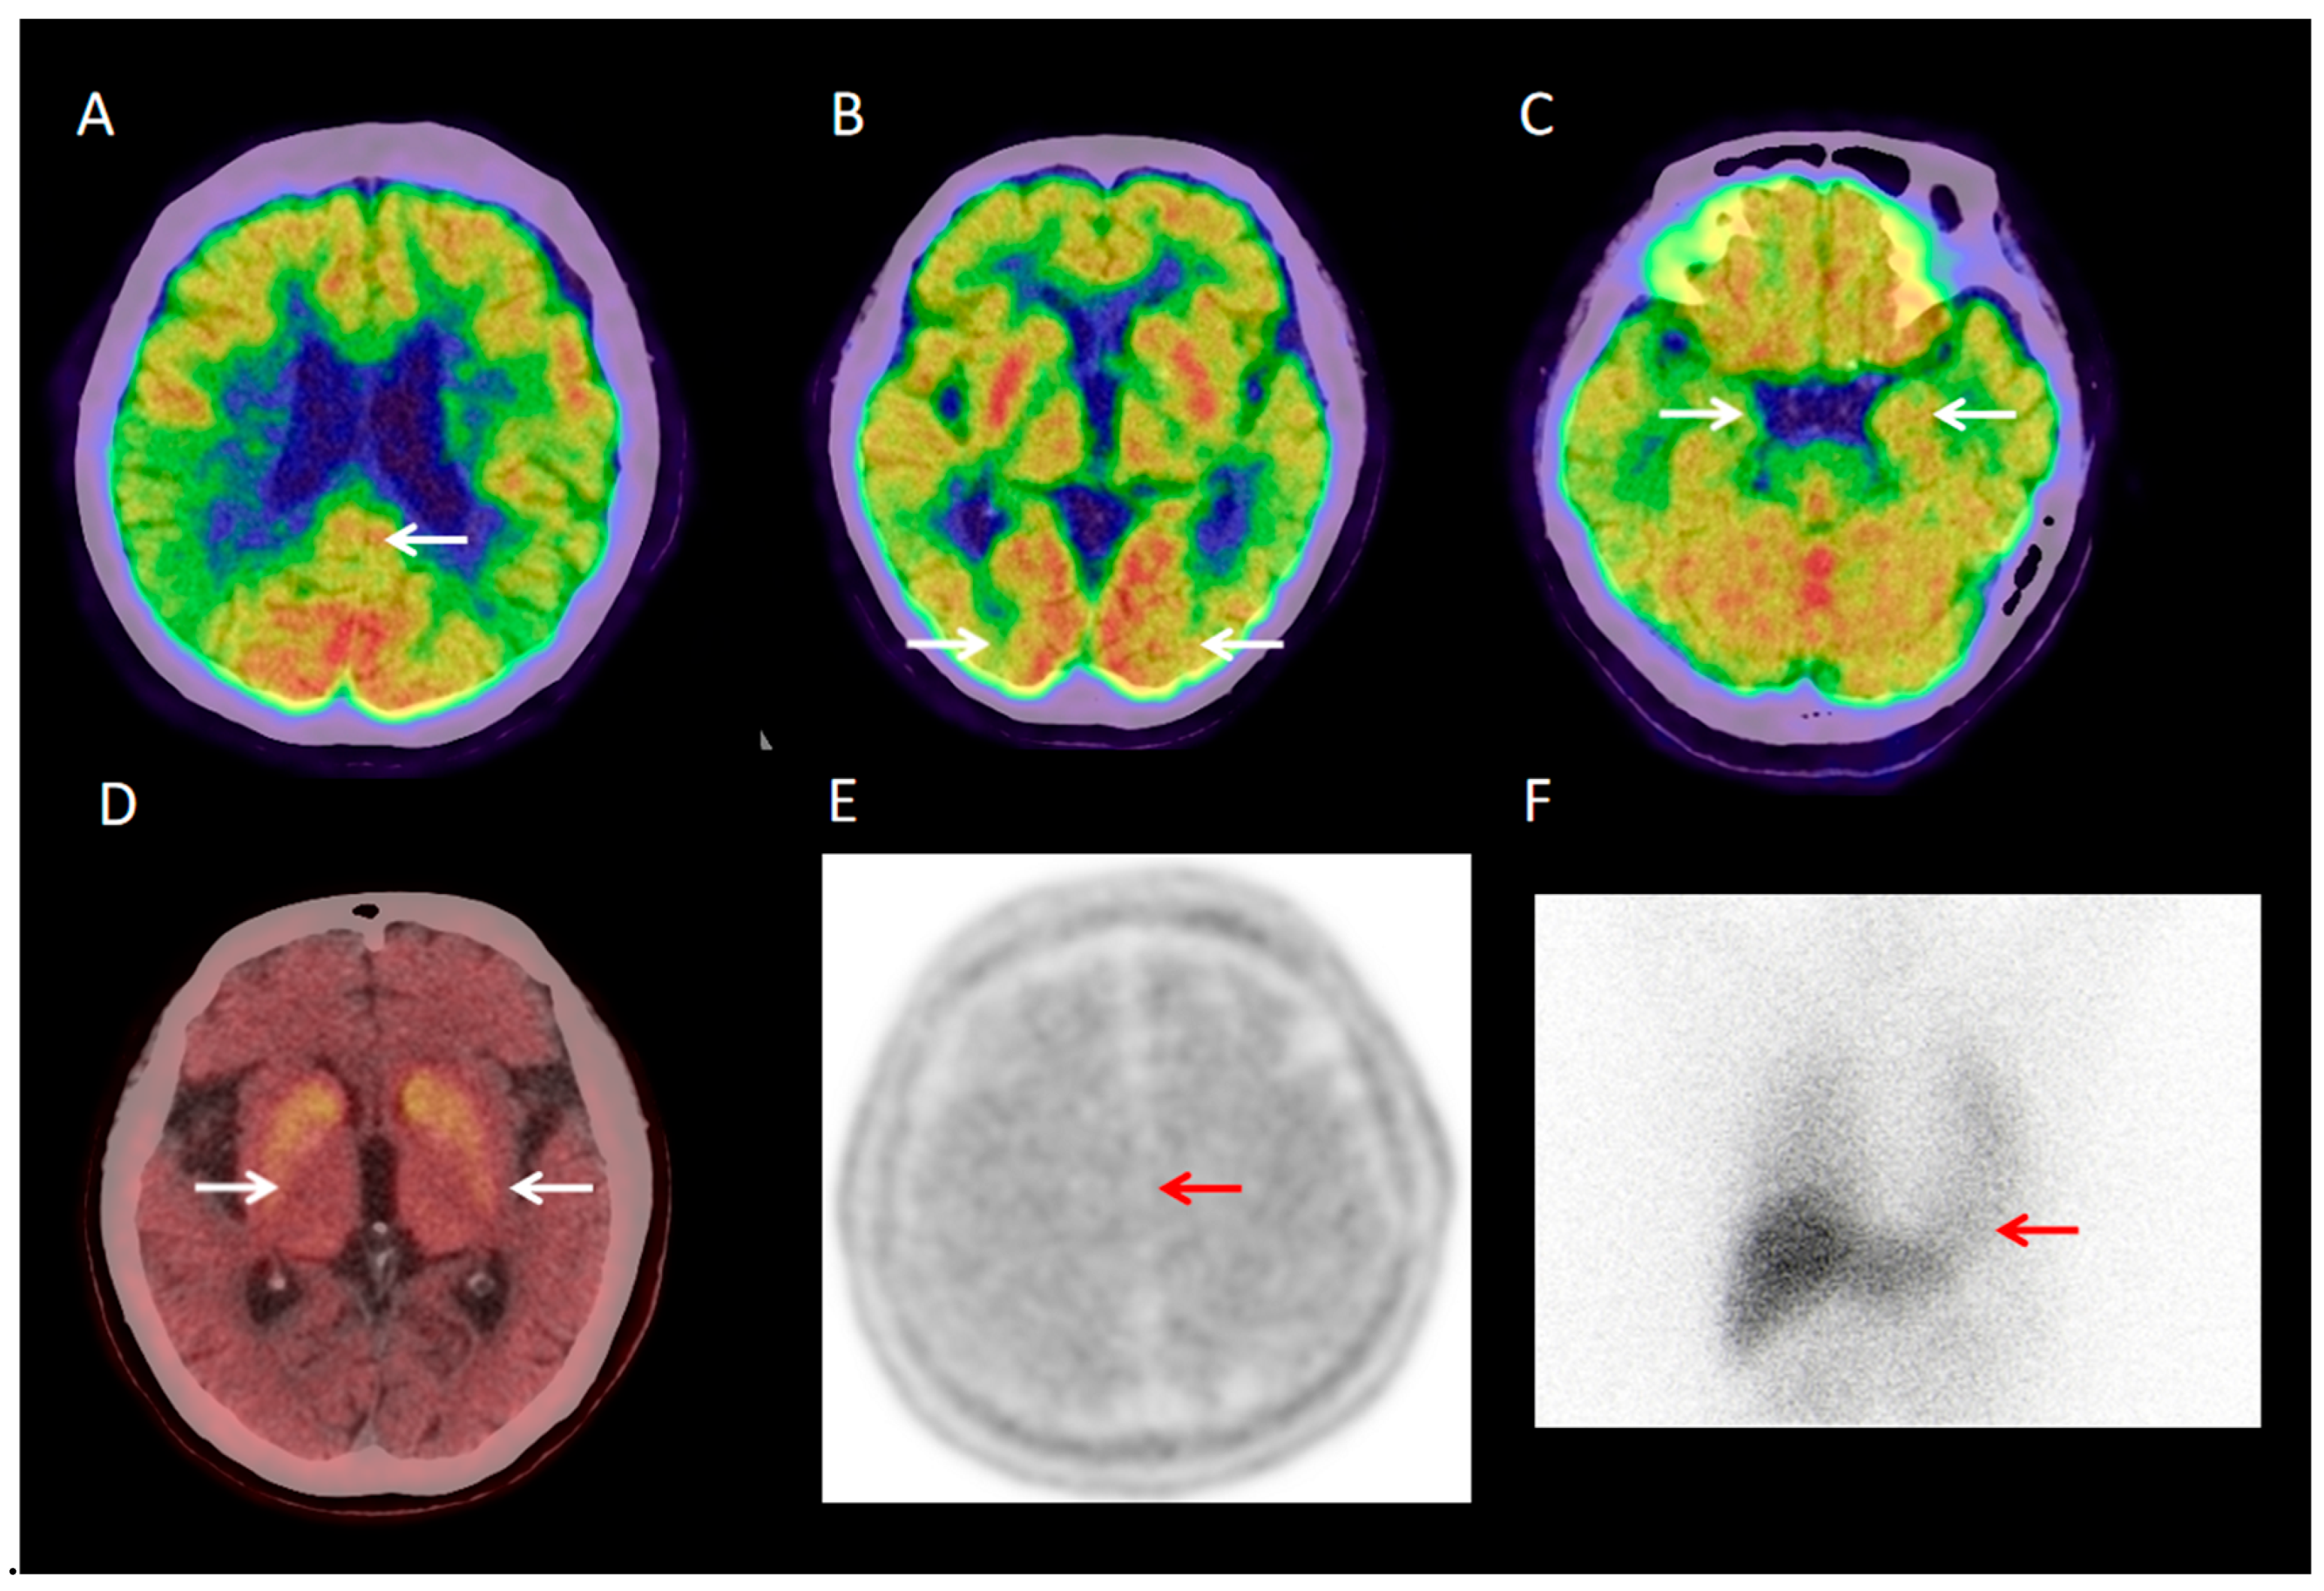

3.2.1. Visual Analysis of 18F-FDG PET/CT

3.2.7. Visual Analysis of 131I-MIBG SPECT

3.2.8. Visual Analysis of 18F-PM-PBB3 PET/CT